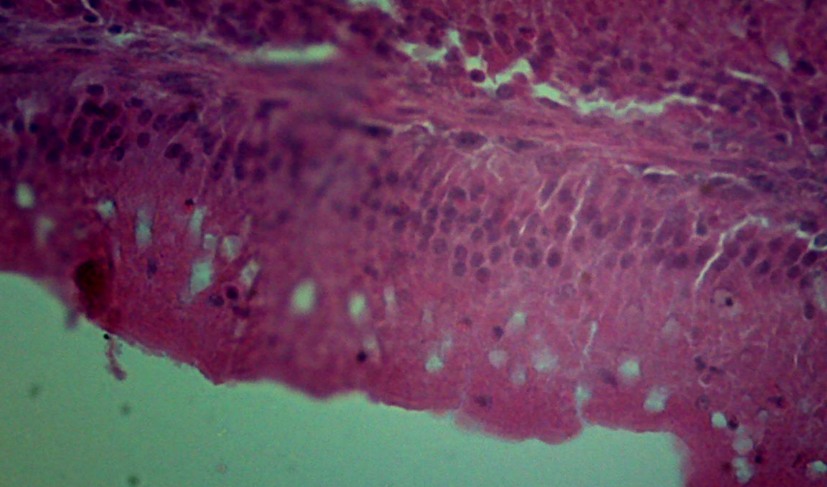

求助 肠道绒毛上的空泡是什么?脂肪变性么? 已有1人参与